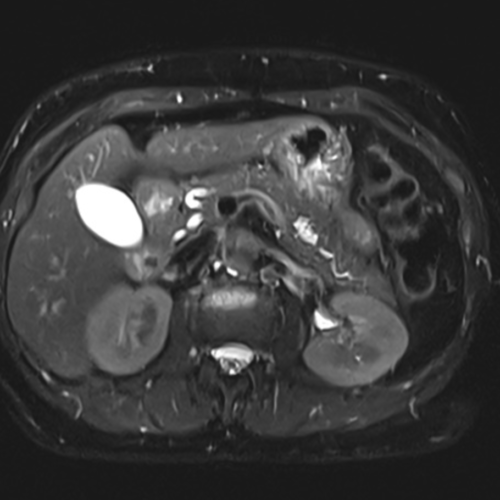

Cet examen est réalisé pour analyser le pancréas et les voies bilaires.

Cette examen permets d’analyser le parenchyme pancréatique et le canal de Wirsung. Il permet de diagnostiquer les cancers, adénocarcinomes du pancréas, TIPMP, cystadénome mucineux et séreux, tumeurs neuro endocrines.